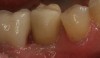

The milled crown is then tried in to verify the fit and occlusion. From the undersurface of the crown, the screw-access hole is located by identifying the extended portion that remained after milling (Figure 6). Using a 0.018-round tapered diamond bur, a hole is placed starting from the internal aspect of the crown surface and carried through the occlusal surface (Figure 7). The access hole is then refined from the occlusal side of the crown with a round diamond bur. The crown is then placed onto the abutment (Figure 8). From an occlusal view, the alignment of the access hole and implant screw is confirmed (Figure 9). The diameter of the hole is enlarged so that the head of the screw can pass through the opening. At this point, the crown can be either cemented onto the abutment or finished, stained, and glazed before cementation.

Fig 6.  An elevated portion (nipple) inside the crown remains after the milling process, which indicates the location of the abutment screw.

Figure 6

Fig 8. After the screw-access hole is placed, the crown is then seated.

Figure 8